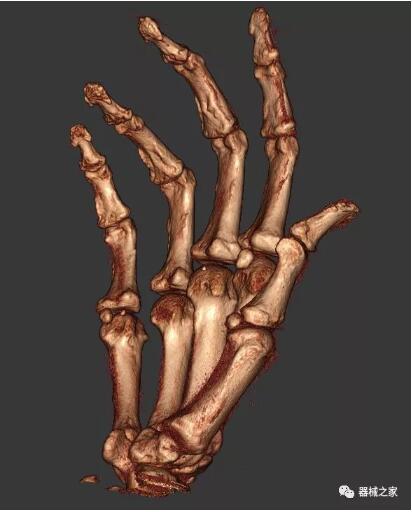

以上介紹的CT均來自國外同一家公司,這些CT均配置了可視化軟件,可以進(jìn)行切片、3D重建以及大型CT附帶的所有典型的操作功能。

以下是這些“特立獨行”的CT所拍出來的圖像: